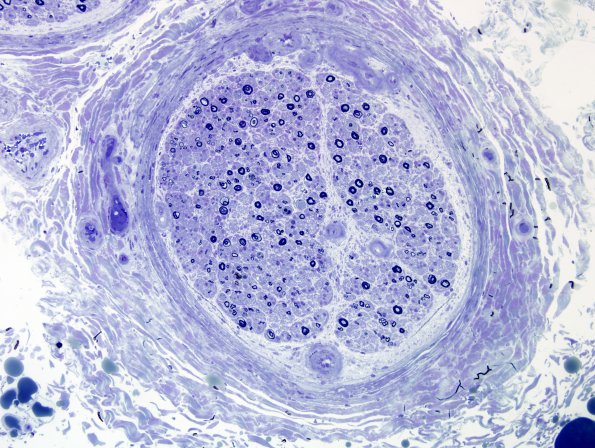

Plastic sections show marked loss of both large and small caliber myelinated axons, although small caliber axons appear to be more severely affected. Many axons appear thinly myelinated for their caliber. There is mild interfascicle and intrafascicle variability in the degree of axonal loss. (Plastic section)